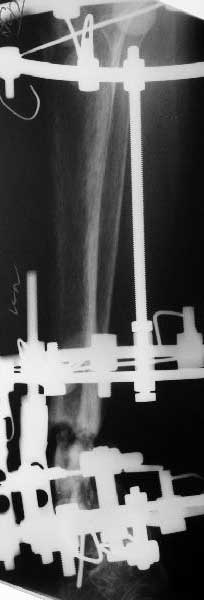

Глубокоуважаемые коллеги,Поступила женщина 72 лет. Полтора года назад - укушенная рана, перелом голени. Лечили аппаратом, не срослось. Долго не заживала рана.

Но вроде уже с полгода мягкие ткани закрыты. Спереди подпаянные рубцы. Есть приличная подвижность на уровне несращения. Картинки в приложении. Что предложите? Спсибо заранее.

Why the need for the Ilizarov if the nonunion is mobile? I would correct the deformity acutely with a fibular osteotomy if necessary to correct the

alignment and proceed with reamed IM nailing if there are no signs or history of infection. Minimum of 2 and preferably 3 distal locks, and put in a big enough nail to get a good isthmal fit. I reported a series of similar cases with an excellent success rate.

Аs you can see it still doesn't allow alignement. So acute correction

will result with equinus. Scars also don't like acute goffer.

My plan is very close to this except staged nailing after 10-15 days

of gradual correction with axial alignment and maybe lengthening.

Closed distraction can provide improvement of local blood supply.